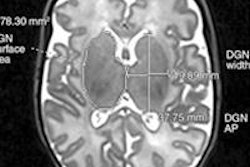

Onyenso received thousands of dollars from Orange MRI for referring Medicare and Medicaid patients for MRI, CT, and ultrasound scans in 2010 and 2011. He was recorded taking cash payments in his Irvington, NJ, office on two occasions, according to federal authorities.